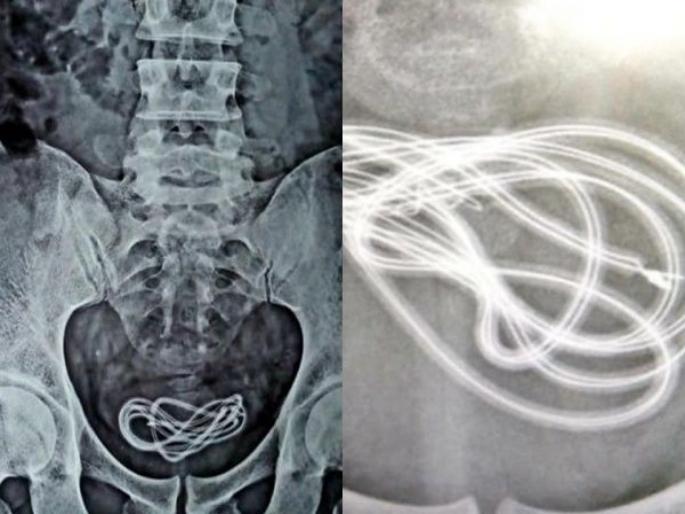

डॉक्टर हैराण तेव्हा झाले जेव्हा त्यांनी एक्स-रे काढला. यात दिसून आलं की, हेडफोनची केबल व्यक्तीच्या पोटात नाही तर त्याच्या मूत्राशयात होती. डॉक्टरांनी सांगितले की, 'मी गेल्या 25 वर्षांपासून सर्जरी करत आहे. पण अशी केस पहिल्यांदाच पाहिली'.

डॉक्टरांनी लिहिले की, या व्यक्तीने चार्जरची केबल तोडांवाटे नाही तर लिंगावाटे आत टाकली होती. त्याची सर्जरी यशस्वी झाली. केबल काढण्यात आली. पण डॉक्टर म्हणाले की, त्याच्या मानसिक स्थितीवर अजूनही प्रश्न आहे.